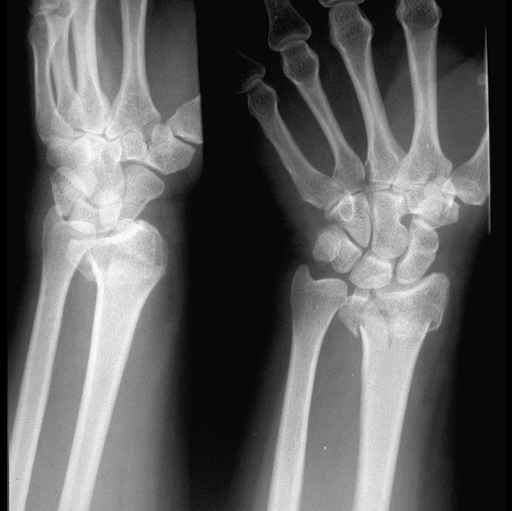

Case 3 Preop

Case3 Preop